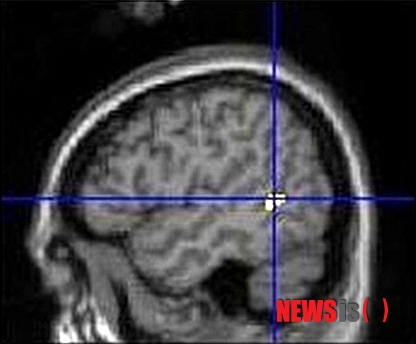

【청주=뉴시스】엄기찬 기자 = 충북대학교병원 정신건강의학과와 청주의료원 소아청소년정신과 연구팀은 25일 기능적 MRI(fMRI) 촬영으로 청소년 인터넷 중독자의 뇌에서 탈신체화 관련 뇌 부위의 활성화가 일반 청소년과 어떻게 다른지를 연구한 결과, 인터넷 중독 청소년의 뇌가 유체이탈 등의 탈신체화 자극에 매우 취약하다고 밝혔다. 사진은 연구팀이 발표한 좌뇌 측두엽-후두엽 연접부의 활성화 모습을 촬영한 사진. (사진=충북대병원 제공)

연구 책임자인 손정우 충북대병원 정신건강의학과 교수는 "청소년에게 공 던지기 애니메이션 게임을 시키면서 탈신체화를 자극했을 때, 인터넷 중독 청소년은 일반 청소년보다 좌반구 측두엽과 후두엽이 만나는 영역, 우반구의 해마 옆, 기타 영역의 뇌 활성화가 현저히 증가됐다"고 말했다.

그는 "이러한 영역들은 탈신체화 관련 주요 부위로 알려졌으며, 이 영역들의 활성화 정도가 인터넷 중독 척도 점수, 인터넷 사용 시간과 유의한 상관관계를 보였다"고 설명했다.